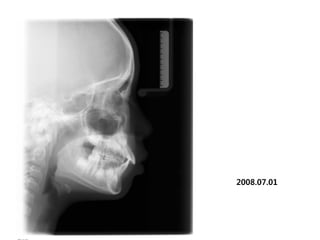

1998.09.25/M

C.C

• Max. protrusion

Dx

• Mentalis action, incorrect tongue posture

Goal

• Establish perioral muscle tone and tongue

posture

2008.07.01

Start T4K

2009.06.23   1y

2010.06.27 2yr

2011 07 28

2012 03 20

out of Tr 2yr